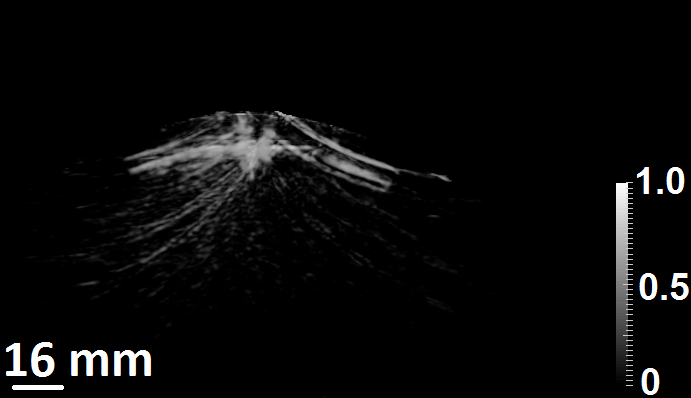

Figure 3: (a) The 3D scanning geometry used for the computer-simulation studies. (b) A 2D slice of X-ray CT image of the skull and (c) the corresponding mask generated by the segmentation algorithm.

The linear isotropic, elastic medium used in the simulation studies was generated from 3D X-ray CT images of a human skull. The intact human skull was purchased from Skull Unlimited International Inc. (Oklahoma City, OK) and was donated by an 83-year-old Caucasian male. The CT images were employed to infer the thickness and contour of the skull.

For the simulation studies involving superscript\mathbb{H}^{\dagger}, we assumed the skull to be an acoustically homogeneous elastic linear isotropic medium. While we consider a relatively simple skull model, the proposed approach could also be applied for more complex skull models, such as those that consider the heterogeneity within the skull. In that case, more effort may be required to accurately estimate the acoustic properties of the skull. In order to extract the contour and location of the skull from CT images, a segmentation algorithm was employed. The segmentation algorithm generated a binary mask specifying the location of the skull within the 3D volume. A 2D slice of the CT image acquired from the human skull and the corresponding mask generated by use of the segmentation algorithm are shown in Fig. 3b and Fig. 3c, respectively. The medium parameters in the 3D grid were assigned such that the skull acoustic parameters (ρ=1850kgm3𝜌1850kgsuperscriptm3\rho=1850\ \frac{\text{kg}}{\text{m}^{3}}, cl=3.0mmμssubscript𝑐𝑙3.0mm𝜇sc_{l}=3.0\ \frac{\text{mm}}{\mu\text{s}}, cs=1.5mmμssubscript𝑐𝑠1.5mm𝜇sc_{s}=1.5\ \frac{\text{mm}}{\mu\text{s}} and α=0.11μs𝛼0.11𝜇s\alpha=0.1\ \frac{1}{\mu\text{s}}) were set at all grid positions where mask was equal to one and the background acoustic parameters (ρ=1000kgm3𝜌1000kgsuperscriptm3\rho=1000\ \frac{\text{kg}}{\text{m}^{3}}, cl=1.5mmμssubscript𝑐𝑙1.5mm𝜇sc_{l}=1.5\ \frac{\text{mm}}{\mu\text{s}}, cs=0.0mmμssubscript𝑐𝑠0.0mm𝜇sc_{s}=0.0\ \frac{\text{mm}}{\mu\text{s}} and α=0.01μs𝛼0.01𝜇s\alpha=0.0\ \frac{1}{\mu\text{s}}) were set at all grid positions where mask was equal to zero. At the material interface between the skull and the background fluid medium, the density and the absorption values were arithmetically averaged to avoid any instability issues with the FDTD wave equation solver.